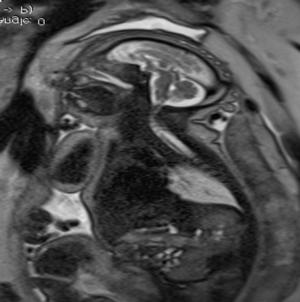

In a third study, ultrasound and fetal MRI were performed on pregnant patients with Zika virus infection at different gestational ages. Once the babies were born, they underwent ultrasound, CT and MRI. The researchers then created 3-D virtual and physical models of the skulls. More than half the babies had microcephaly, brain calcifications and loss of brain tissue volume, along with other structural changes.

"The emergence of Zika virus in the Americas has coincided with increased reports of babies born with microcephaly," said study author Heron Werner Jr., M.D., Ph.D., from the Department of Radiology at Clínica de Diagnóstico por Imagem. "An early diagnosis may help in treating these babies after birth. Moreover, the knowledge of abnormalities present in the central nervous system may give hints about the pathophysiology of the disease."